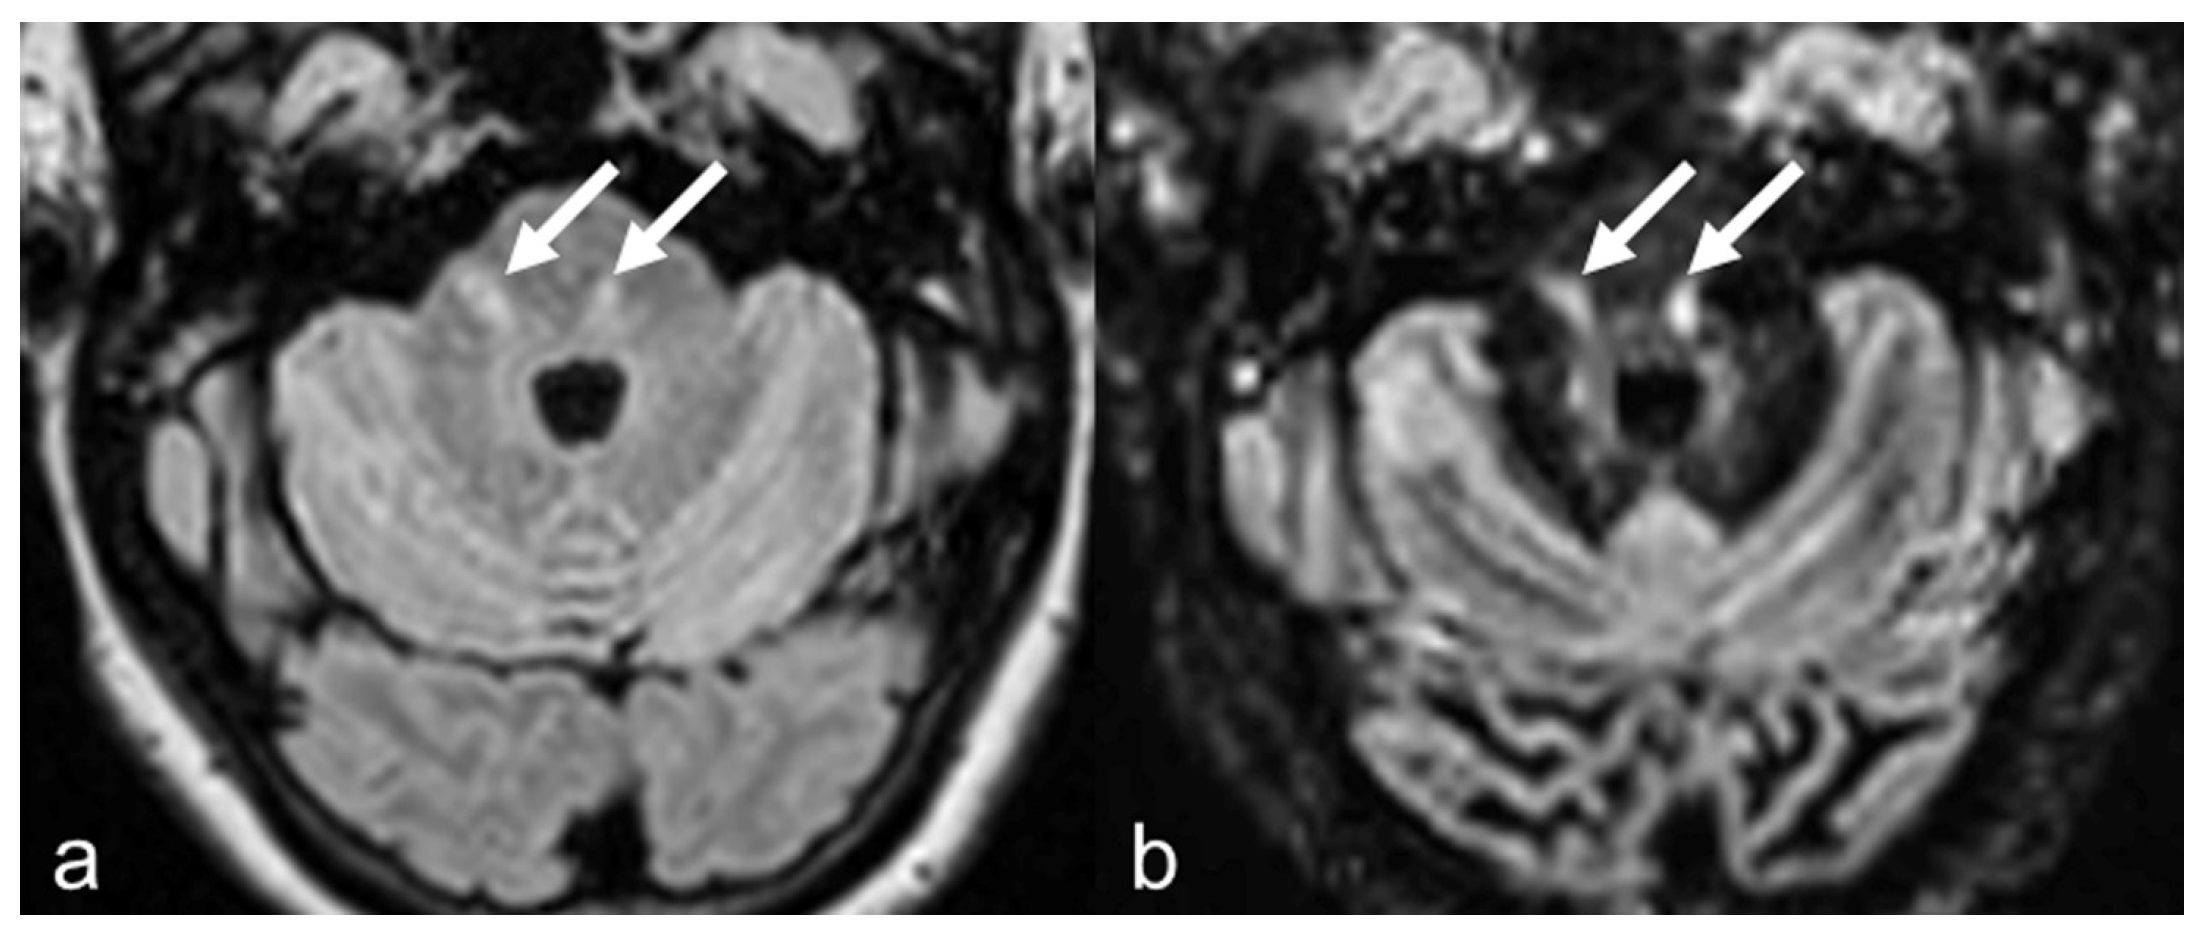

| In MS protocol, attention has to be paid to perform DIR before contrast-administration, as post-contrast DIR may suppress active subcortical lesions. |